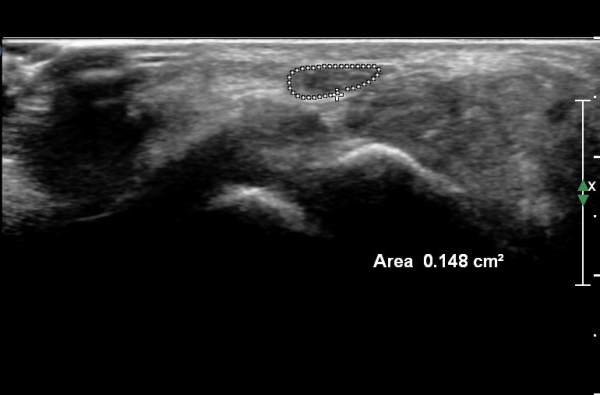

ÃÊÀ½ÆÄÀ¯µµÇÏ Á¤Áß½Å°æ ¼ö¾×¹Ú¸®¼ú(÷ºÎ »çÁø Âü°í) »çÁø¿¡¼ Á¤Á߽ŰæÀÇ Ç¥Ãþ¿¡ ÁÖ»ç¹Ù´ÃÀÌ À§Ä¡Çϰí

ÁÖ»çµÈ ¼ö¾×¿¡ ÀÇÇÑ È¾¼ø±Ù Àδ밡 Á¤Á߽Űæ°ú ºÐ¸®µÇ´Â ¸ð½ÀÀÌ º¸ÀÓ(»çÁø 6, 7, ÷ºÎÆÄÀÏ µ¿¿µ»ó). ½ÃÇàÇÏÁö ¾ÊÀ½.